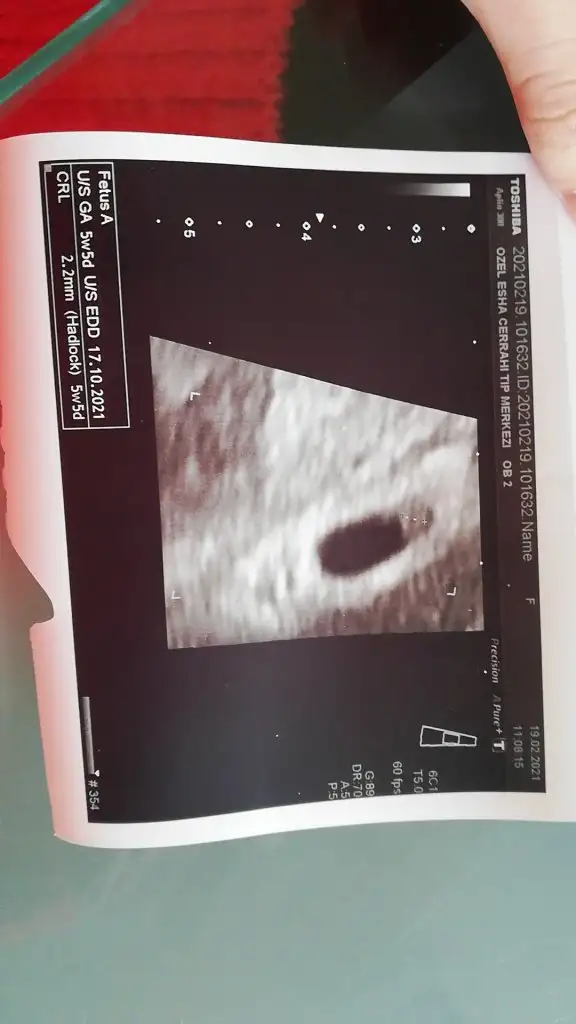

Kız bebek6 hafta